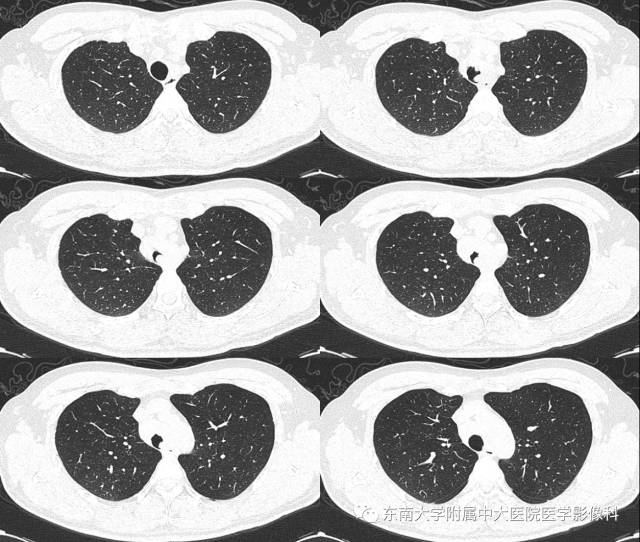

病例1

病史

男,35岁,因“反复咳嗽气喘1年余”入院。1年余前出现咳嗽气喘,咳嗽为阵发性干咳,感冒后加重,气喘多为活动后出现,自诉能听到哮鸣音。肺功能示:FVC%Pred 40%、FEV1%Pred 19%、FEV1/FVC% 80.9%,混合性通气功能障碍,支气管舒张试验阴性。

CT

平扫 增强